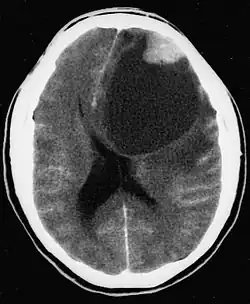

| CT scan of a brain with pleomorphic xanthoastrocytoma. The classic radiographic appearance is one of a superficially situated tumor, here a mural nodule, associated with an underlying cyst. |

Pleomorphic xanthoastrocytoma usually develops within the supratentorial region (the area of the brain located above the tentorium cerebelli). It is generally located superficially (in the uppermost sections) in the cerebral hemispheres and involves the leptomeninges. It rarely arises from the spinal cord.